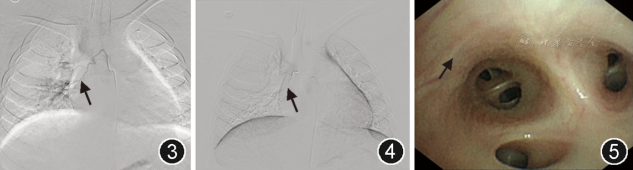

经多学科讨论后,决定行支气管动脉数字减影血管造影(digital subtraction angiography,DSA)及支气管动脉栓塞术(bronchial artery embolization,BAE)。DSA显示右侧支气管动脉异常迂曲扩张,一支血管走行与支气管镜下病灶位置相符,并呈恒径畸形(图3)。采用微导管超选至靶血管,注入Onyx胶进行栓塞。术后即刻DSA复查显示异常血管完全闭塞,未见造影剂外溢(图4)。术后患者未再咯血,生命体征平稳,血红蛋白逐渐回升。术后3 d复查支气管镜,原黏膜下隆起病灶消失(图5),双侧主支气管及各叶段支气管管腔通畅。随访15个月,患者无咯血复发,恢复良好。

图3  DSA(支气管动脉栓塞前)可见右侧异常扩张扭曲的支气管动脉(箭头示)

图4  支气管动脉栓塞后DSA显示右侧异常扩张的支气管动脉影消失(箭头示),近端支气管动脉内可见沉积的Onyx胶影

图5  畸形支气管动脉栓塞后支气管镜下可见右上叶开口处原黏膜下隆起的病灶消失(箭头示)

DSA可能显示恒径动脉或异常扩张的支气管动脉[2,17, 18, 19]。病变血管多来源于支气管动脉,表现为管径未逐渐变细的恒径动脉畸形,呈丛状、环状或球状扩张[19]。在活动性出血时,造影剂可从黏膜下畸形动脉直接外溢至支气管腔内,形成“喷射样”或“涌血”征象。与结核、支气管扩张等所致血管畸形不同,TBDD通常病灶局限,周围不存在其他病灶,无多发支气管动脉扭曲畸形、支气管肺动/静脉瘘、胸廓内动脉及甲状颈干等其他动脉畸形[17, 18, 19]。本文病例也为局限性支气管动脉畸形病灶,周围没有其他病变。

TBDD主要的治疗方法包括支气管动脉栓塞术(BAE)和外科手术[1, 2,10,21]。BAE的优点是微创,能即时止血,快速控制急性大咯血,并为外科手术创造机会,减少急性大出血时外科手术的高病死率,但部分患者可能因栓塞不彻底、栓塞后再通或侧支循环形成导致复发。Onyx胶、NBCA胶等永久性液体栓塞材料可能栓塞更彻底、更少复发,但需进一步临床研究证实。笔者在所报告的患者中采用了Onyx胶栓塞,已15个月尚无咯血复发。外科手术可行病灶局部肺叶切除,适用于反复出血、栓塞治疗失败或病变局限者,可根治疾病,但创伤相对较大。具体采用何种治疗手段应依据个体化策略而定[1]。